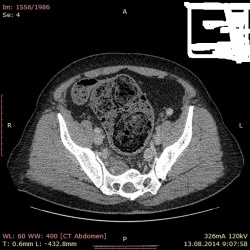

21.10.2014 - 22:56

Пациент 13,08.2014 прошел исследование КТ ОБП выставлено заключение парапроктит, ретроректальный абсцесс, киста Тарлова, деструкция крестца, мегаколон (в детстве болезнь Гиршпрунга). Как...